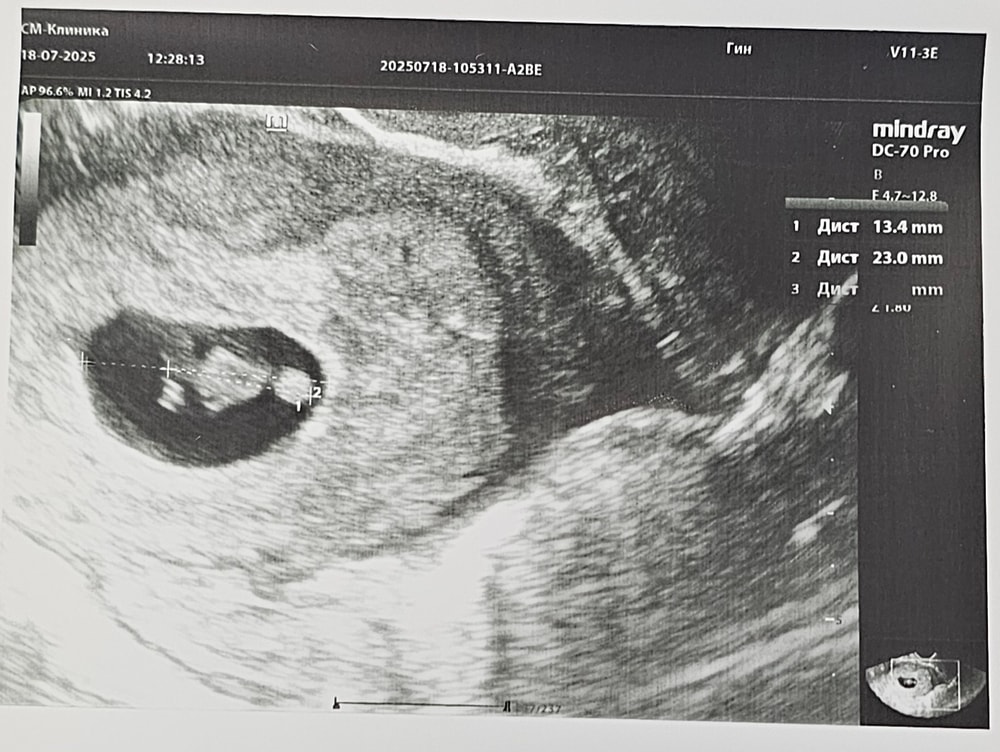

Узи 7/8 недель

Беременность- 1 триместр ( только до 10 недель)Срок по мес 8 недель ровно, по узи 7 полных недель. Совпадает с моей поздней овуляцией.

Плодное 23 мм

КТР 13,4 мм

СБ 157 уд/мин

К измерениям отношусь без излишней тревожности, узисты разные, каждый меряет по своему. В жк 10.07 мне плодное написали аж 17,2. Явно больше сегодня должно бы быть) Но вроде разница между плодным и эмбрионом нормальная, место есть для роста.